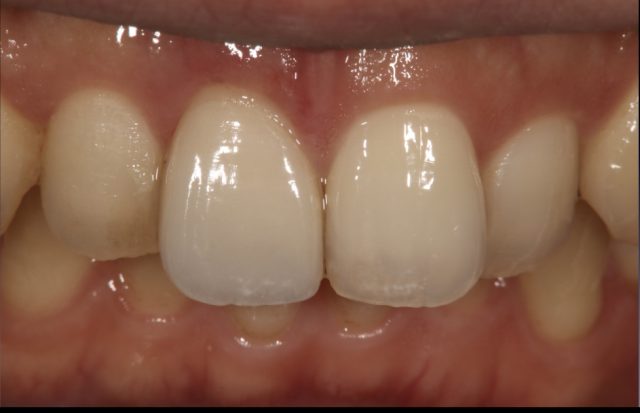

| 診断名 | ラミネートベニア(1本) |

|---|---|

| 年齢・性別 | 20代・男性 |

| 治療期間・回数 | 2週間~3週間/2回 |

| 治療方法 | ラミネートべニアで審美修復 |

| 費用 | 132,000円(税込み) |

| デメリット・注意点 | 保険が適用できないため自費診療になる。 セラミックスインレー・クラウンに強い力がかかると割れてしまう恐れがあるため、歯ぎしりや食いしばりが癖になっている患者様にはおすすめできない場合がある |